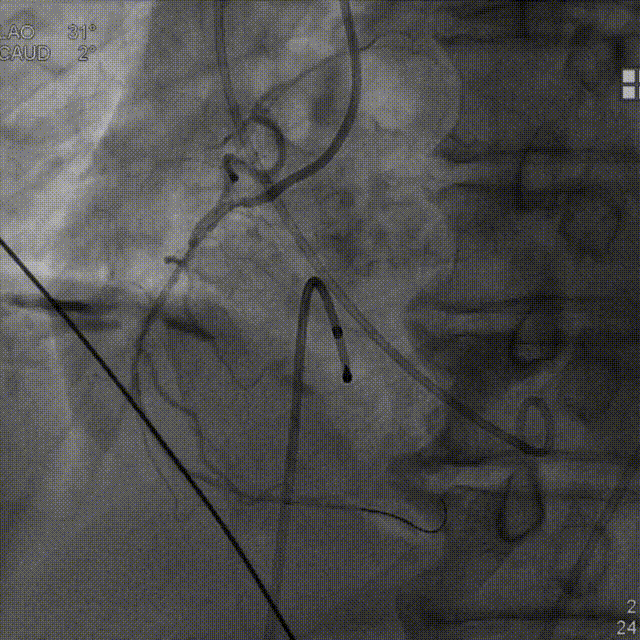

术前平均跨瓣压差36.7mmHg,左室射血峰值流速303cm/s,造影示明显反流。

两次球扩,第一次向主动脉内滑脱,第二次球囊扩张真诚,未见明显腰征,按术前评估选择AV29号瓣膜。

造影下第一次释放,定位不理想,回收后预备重新释放。

精准再定位,释放于预定位置,瓣膜工作状态良好,造影示微量瓣周漏。